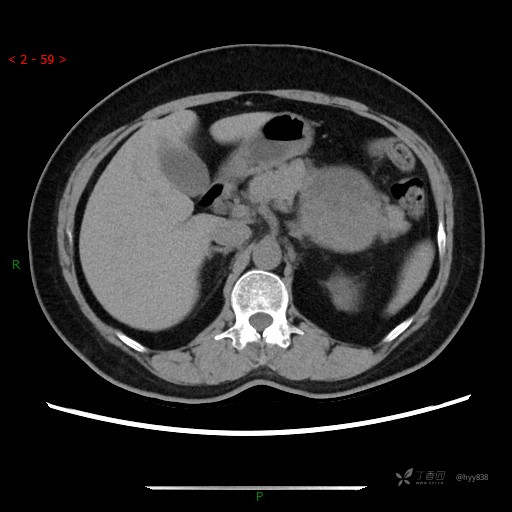

中腹部CT平扫